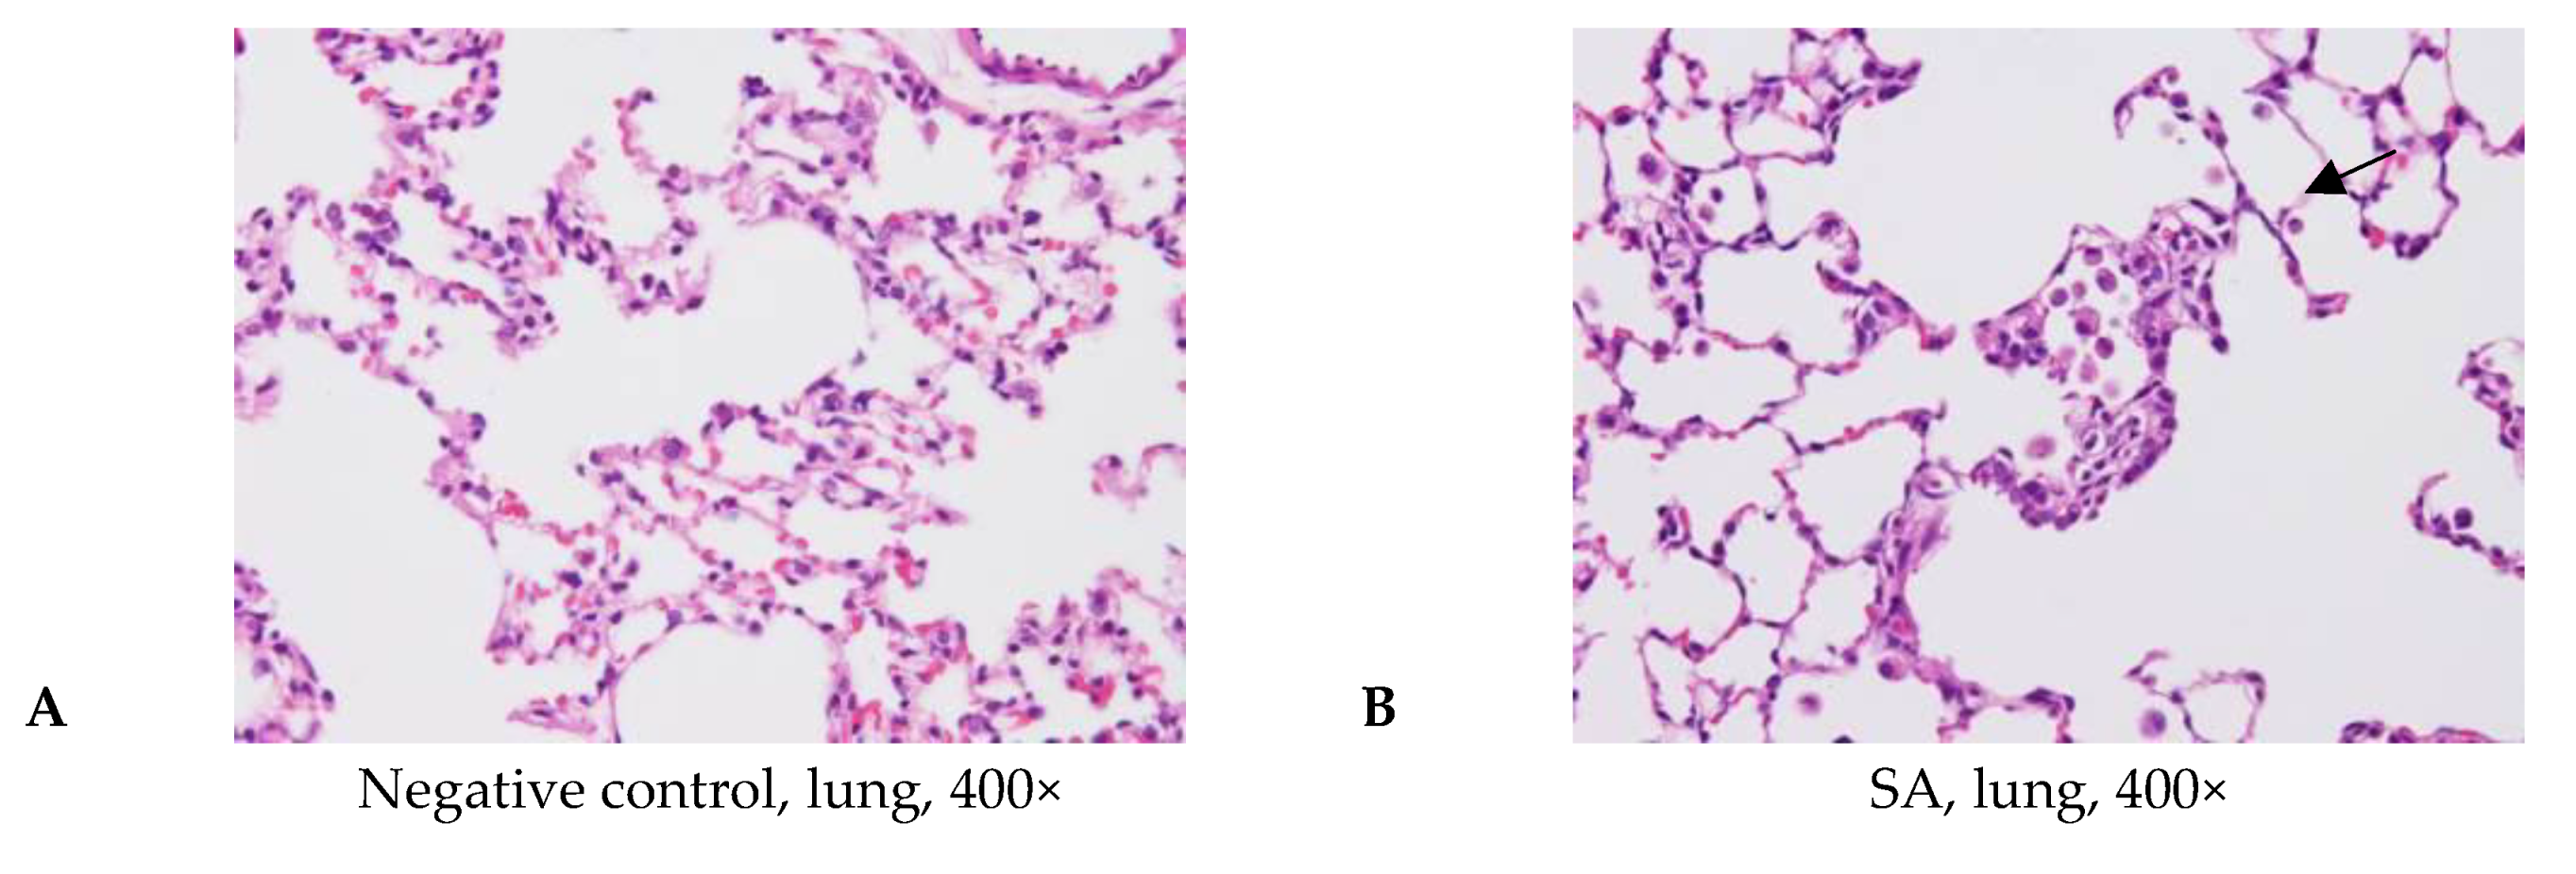

3.4. Acute Pulmonary Toxicity Test (1 D)

3.5. Acute Pulmonary Toxicity Test (14 D)